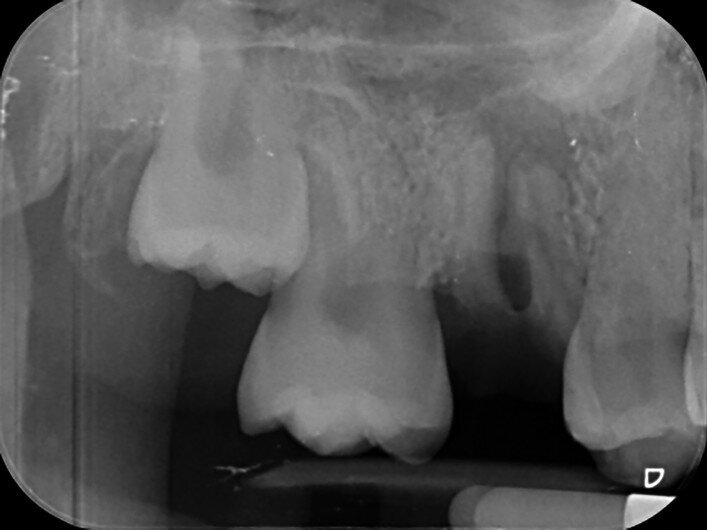

Fig. 3: Pre-op periapical radiograph.

A 47-year-old male patient in a good medical condition and a non-smoker was referred to our dental practice for endodontic retreatment of the right maxillary second molar. The dental history revealed that the tooth had been endodontically treated three months before because of acute pulpitis. After the treatment, the patient complained of pain on chewing. Antibiotics and a non-steroidal anti-inflammatory drug were prescribed, but the pain remained. After a month, a sinus tract appeared. The tooth was retreated in another practice without success. The clinical inspection revealed the presence of a sinus tract near the apical region of tooth #17. The tooth had been prepared for a full crown, but was without even a temporary crown, and the access cavity had been closed with temporary filling material. Cracks were evident on the buccal and mesial surfaces. Periodontal probing showed a deep pocket (> 12 mm) on the distal aspect of the root trunk (Figs. 1 & 2). The periapical radiograph showed a radiolucency between the roots of the second and third molars. The radiographic appearance of the endodontic treatment was good, without clear evidence of periapical radiolucencies (Fig. 3). A perforation of the pulp chamber floor was suspected. A CBCT scan was performed (Figs. 4–7), and it confirmed the suspicion of perforation, along with the presence of a large periradicular radiolucency and an unfavourable root shape.